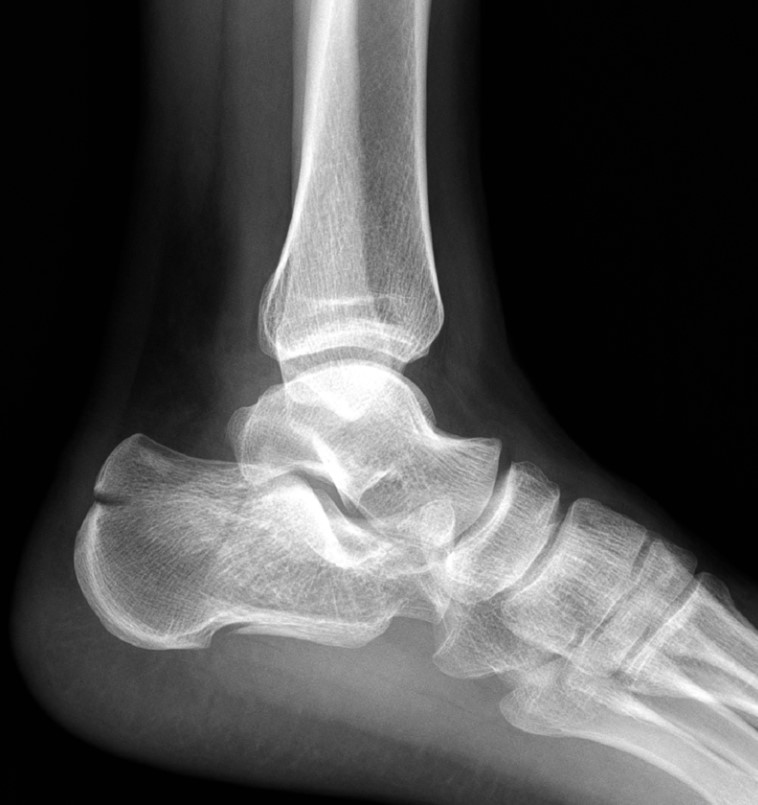

Рентгенівські промені пронизують плоть, малюючи портрет катастрофи на плівці чи екрані. Тіні і світло складаються в історію перелому.

Але рентген — лише силует, тінь реальності. Справжню карту руйнувань малює комп’ютерна томографія (КТ) — безжальний картограф, що шар за шаром зрізає тканини, показуючи перелом у всій його тривимірній жорстокості. Тут видно кожен уламок, кожну тріщину, кожне зміщення. КТ дозволяє побачити те, що приховане від звичайного погляду — як суглобова поверхня розламана на шматки, наче дзеркало, що впало на підлогу.

Саме ці знімки визначають, чи зможе лікар зібрати цю «складанку» назад, чи доведеться жити з компромісом.